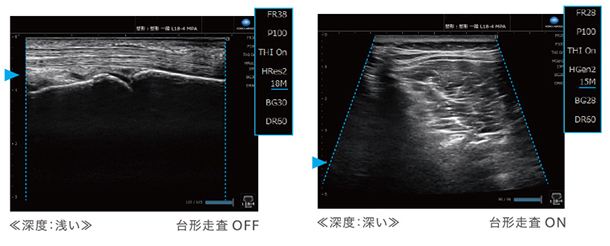

コニカミノルタの高感度・広帯域プローブ「L18-4」と,独自の波形生成技術,信号処理技術を組み合わせ,コントラスト分解能・空間分解能の高い鮮明な画像を提供します。